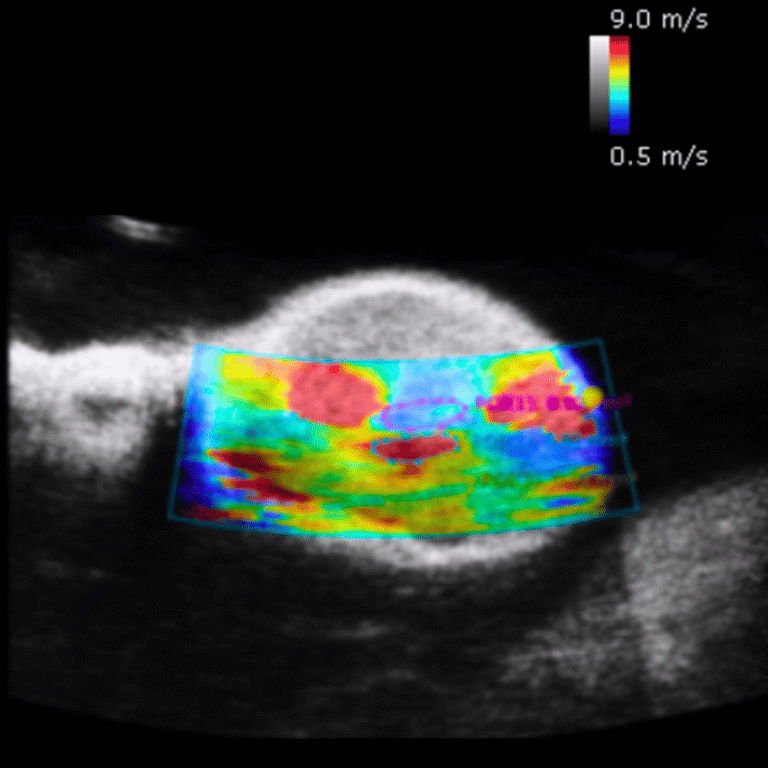

🫀 2. Hemodynamic Measurements in Small Animals Are Not Accurate with Clinical Systems

Clinical ultrasound is designed for imaging humans, not small animals with organs and vessels only millimeters, or even microns, wide. These systems typically operate between 2–15 MHz, which is far too low to resolve fine anatomical structures in mice or rats.

Preclinical ultrasound systems, on the other hand, operate at 15–50 MHz, enabling:

• High-resolution micro-anatomical imaging

• Precise visualization of vessels, valves, and soft tissues

• Improved ability to quantify subtle physiological changes

Without this resolution, many preclinical findings risk being missing or inaccurate.